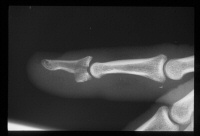

| Case 1. This patient sustained a closed comminuted fracture of the distal phalanx with dorsal-palmar split of the base and a completely displaced transverse fracture of the diaphysis. |

| Inury. |